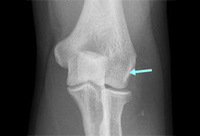

AP radiograph of elbow with lateral calcification from chronic lateral epicondylitis

From the collection of Daniel J. Solomon, Naval Medical Center San Diego, CA; used with permission